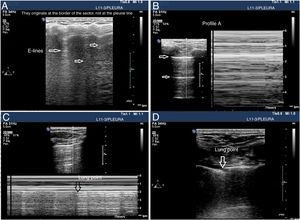

The patterns of airing of each pulmonar region are (Fig. 2):

Pattern A: typical pattern of normal airing. Pleural line with preserved sliding, presence of well spaced A-lines and ≤ 2 B-lines (Fig. 2A and figure B).

Pattern B1: presence of more than 2 well spaced, diffuse B-lines in different thoracic regions called septal rockets (Fig. 2C).

Pattern B2: confluent B-lines separated between them by ≤ 3mm (ground-glass rockets) due to a more severe loss of aired lung (Fig. 2D).

Pattern C: lung consolidation suggestive of significant loss of airing of the lung due to the accumulation of fluid and/or cells in the alveoli. The consolidation can be found anywhere in the hemithorax but applying the transducer to the PLAS point detects 95% of the cases (Fig. 2E and figure F).

Patterns of airing of the pulmonary region. A) Typical pattern of normal airing (profile A in the BLUE protocol) showing 2D imaging. B) Pattern A on M-mode. C. Pattern B1. D) Pattern B2. E) Pulmonary consolidation (profile C in the BLUE protocol) showing shred sign. F) Air bronchogram. A, B, C, D, and E: linear probe study; F, convex probe.

Patterns A, B1, and B2 include the presence of lung sliding (Appendix B annex 3 of the DSD).

In the case of patients with COVID-19 the typical findings are based on disease progression. The first signs on the PU show an irregular distribution of focal B-lines, later confluent, that spread towards several regions of the pulmonary surface. Disease progression is represented by the appearance of small subpleural consolidations with a thickened and irregular pleural line and areas associated with white lung, regions with pattern A patches, and anomalous areas without massive PE. Disease progression will show a consolidation pattern, especially in dependent regions of the body with or without air bronchogram and its increasing spread across the pulmonary surface, indicative of progression to ARF that may require MV.